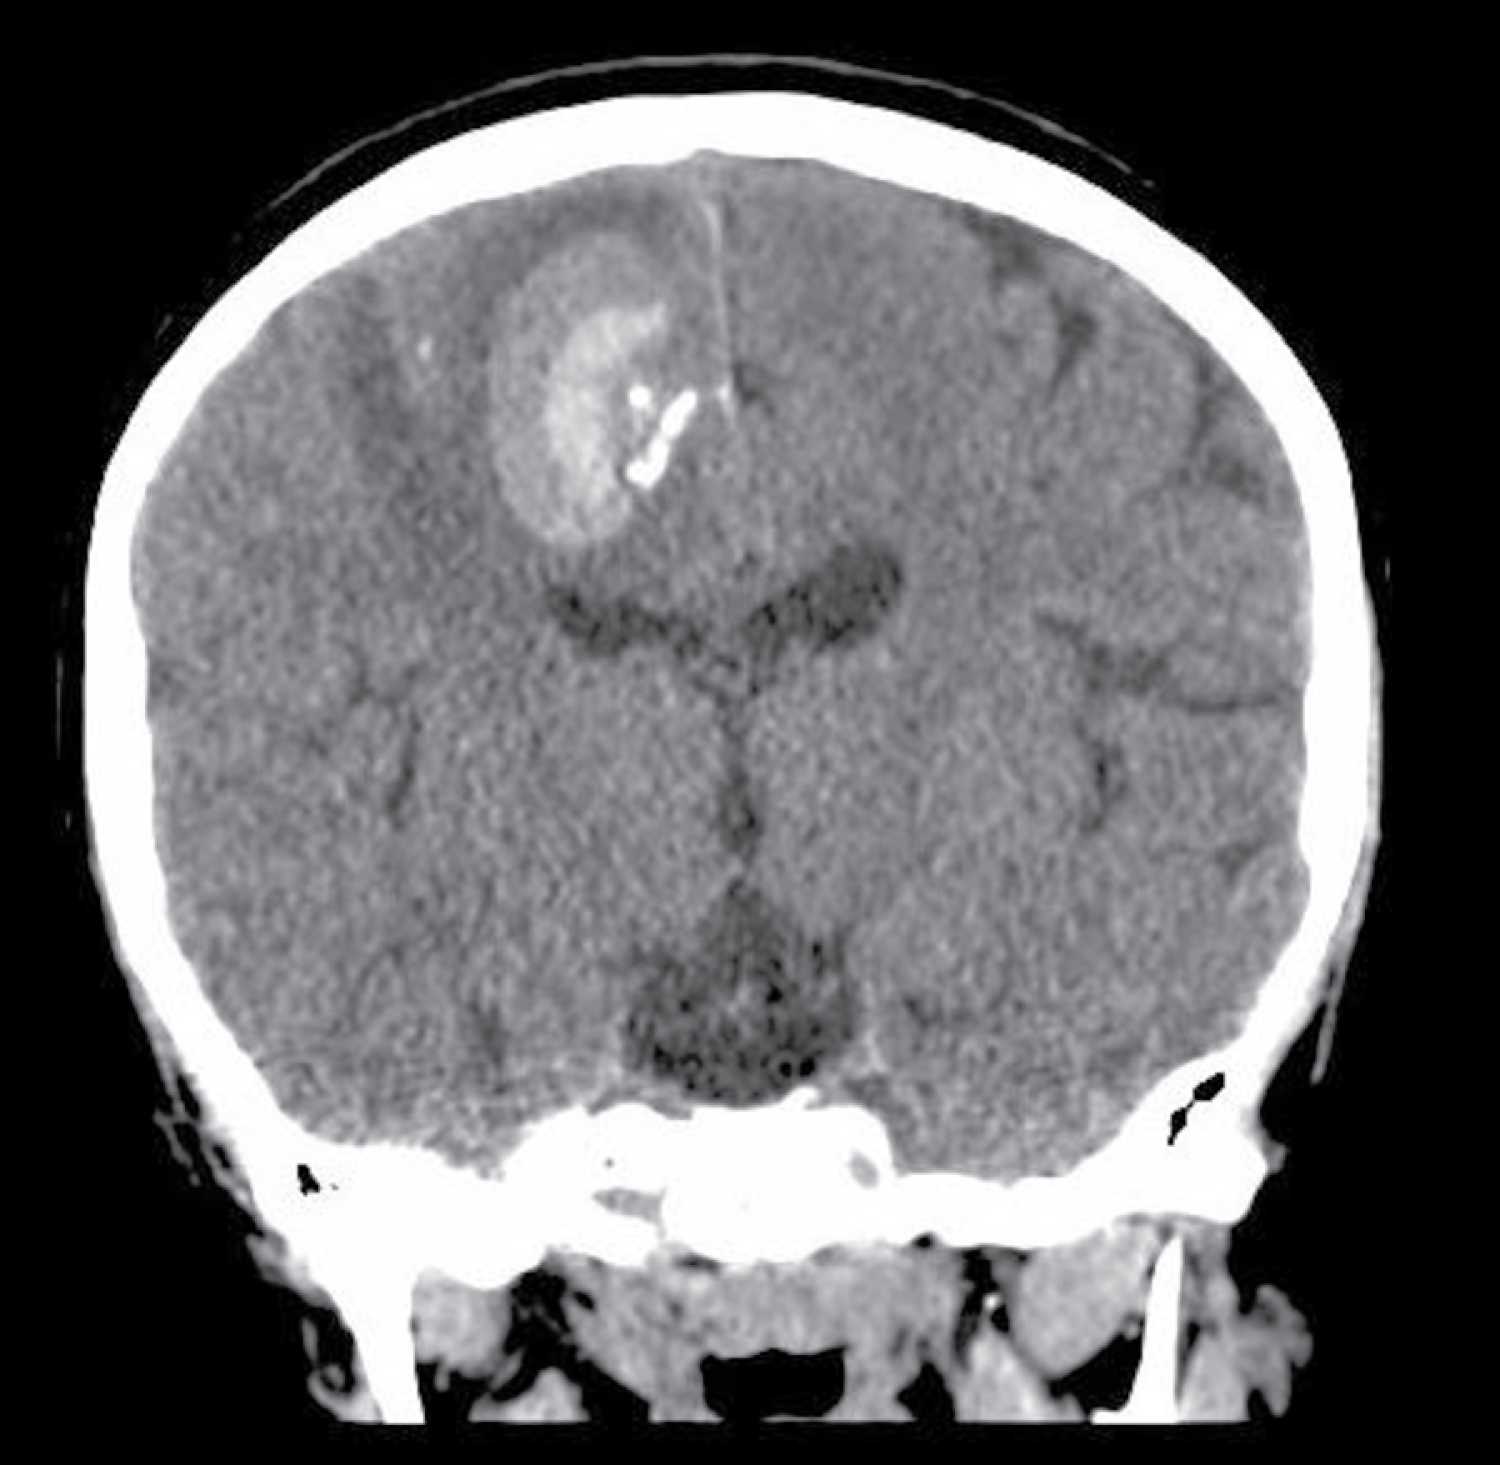

In the 2 weeks prior to her presentation to our ED, she had increased frequency of generalized seizures. Seizures lasted 1-2 minutes with horizontal gaze deviation and generalized convulsions. She presented to the ED with left hemibody weakness and numbness. Physical exam showed paralysis, hypotonia, and sensory deficit of the left side of the body. Exam also showed a hyperpigmented indurated plaque beginning at the nasal bridge, slightly to the right of midline, which extended towards the vertex past the hairline (Figure 1). Head CT (Figure 2) showed a 2.3 × 2.3 × 2.3 cm area of hemorrhage and surrounding vasogenic edema in right parietal lobe, which prompted a workup for vascular cause. Differential diagnoses included mycotic aneurysm, AVM, or cavernoma. CTA Head was negative for vascular malformations. MRI indicated multifocal areas of right frontal, parietal, and temporal parenchymal calcifications. Endovascular catheterization and angiography of the cerebral vessels was performed twice without showing evidence of vascular malformations.

Figure 2: Coronal slice from head CT showing intraparenchymal hemorrhage in the right parietal lobe of a patient with ECDS. View Figure 2